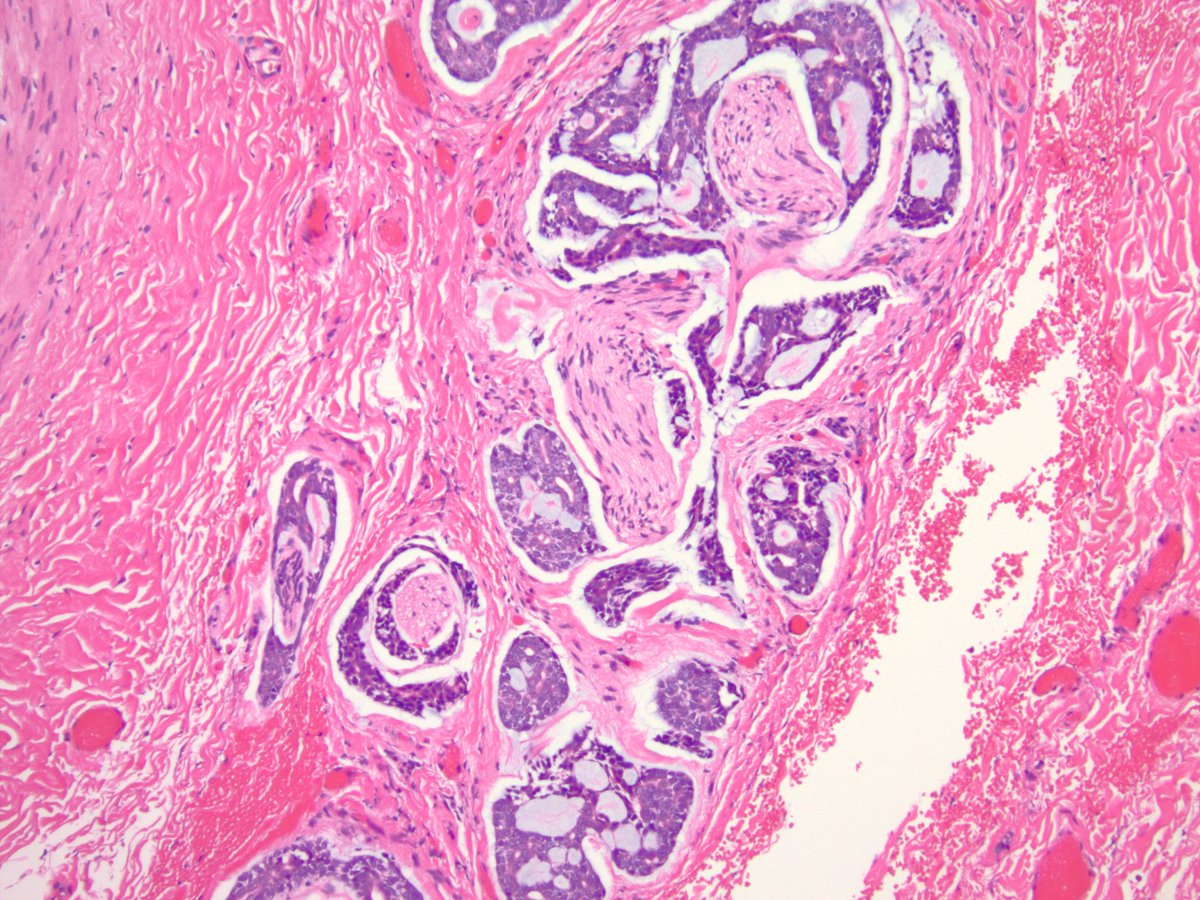

Nasopharyngeal CA (Pics: HP, LP, p40, and EBV ISH).  These can be very tricky as the tumor can be very subtle! Noteworthy feature in this case was the presence of concomitant granulomatous reaction (see PMID 1717637 and 32562216) #PathTwitter #pathology